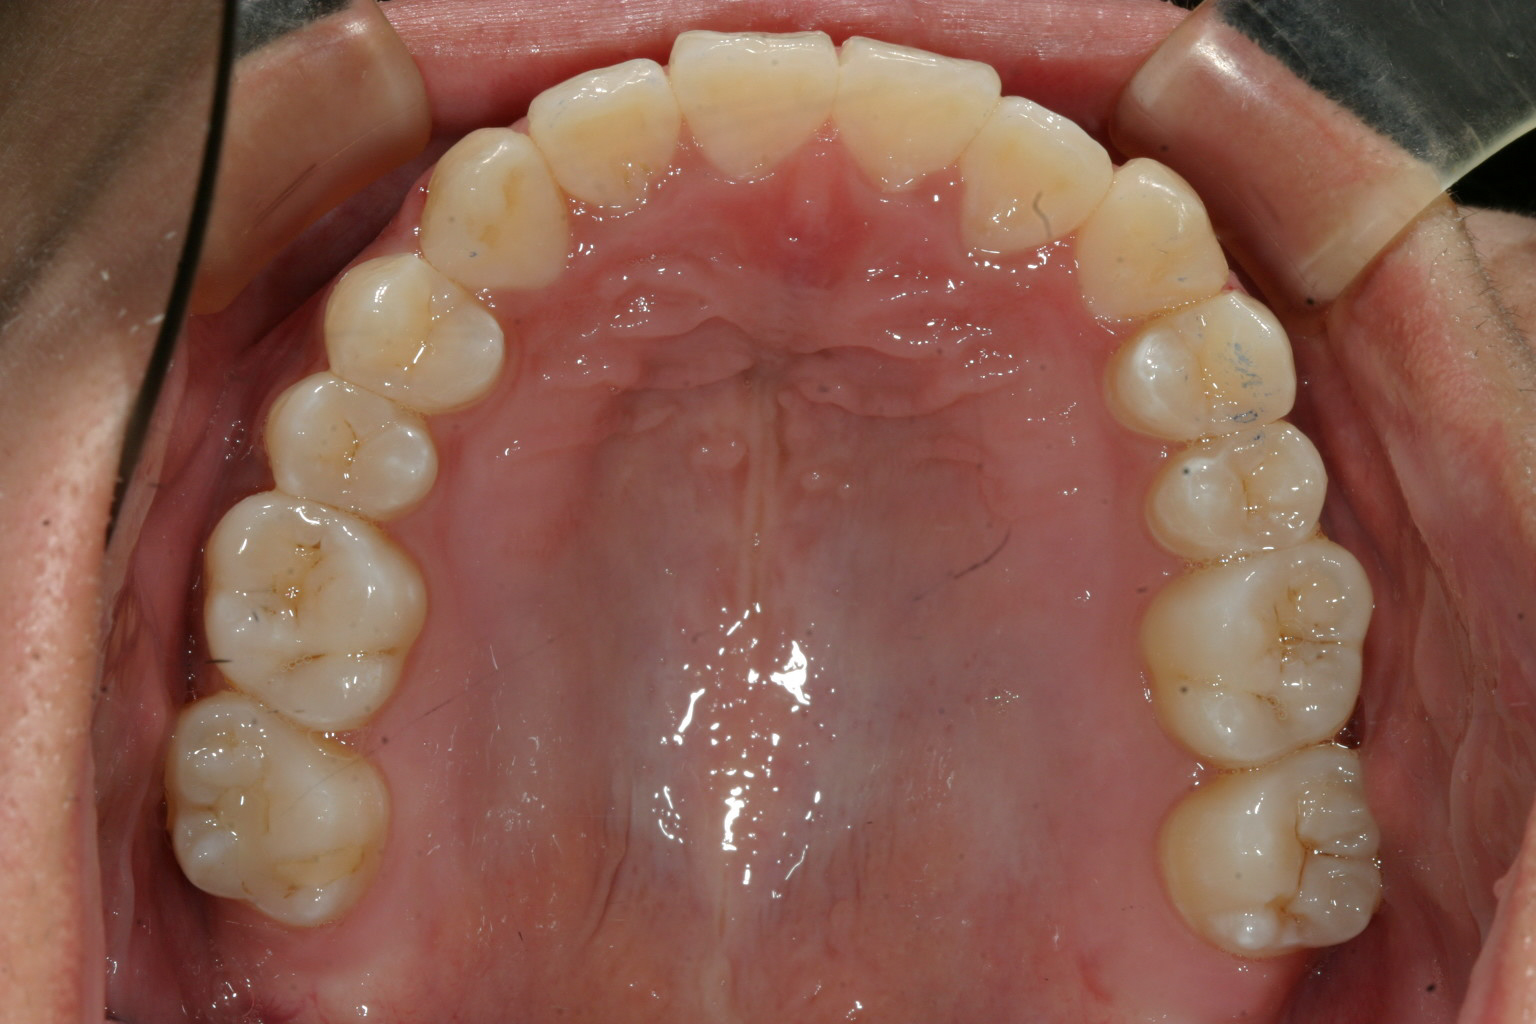

飛び出た犬歯もアーチに入り綺麗に並びましたね!

叢生も綺麗になっています。

上下の被蓋関係も良好です。

今回のインビザラインケースは上顎犬歯の飛び出し改善です。

非抜歯で行いましたが加速矯正装置無しでしたから結構の時間がかかりました。

この様な複雑なケースは加速矯正装置を使用すべきだったと後で思いました。

しかし患者様の並々ならぬ努力があり綺麗に改善し喜んで頂いています。

今回の様に糸切り歯が飛び出した場合、綺麗にアーチに修める手助けとしてゴムの力を利用します。

又、最終的に奥歯全体的に上手く噛ませるのにもゴムの力を利用しました。